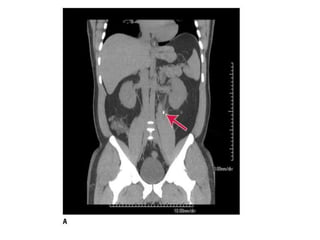

BT

• Non-kontrast helikal BT sensitif ve spesifiktir

Görüntüleme • • • • • Taşın varlığını kanıtlar Diğertanıları dışlatır komplikasyonIarı öngörür. Taşı lokalize eder Tedaviyi öngörür.

BT • Non-kontrast helikalBT sensitif ve spesifiktir